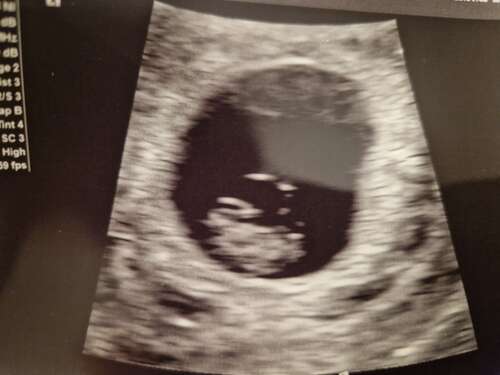

9+2 inwendig van rugaanzicht. Baby was lekker veel met zijn armpjes en beentjes aan het bewegen, zo leuk om te zien 🥰